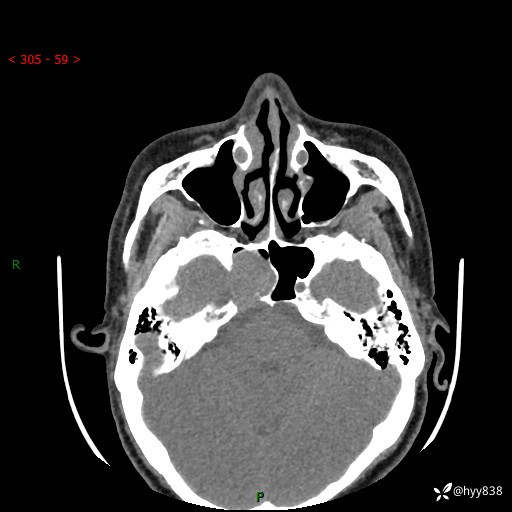

蝶鞍CT平扫